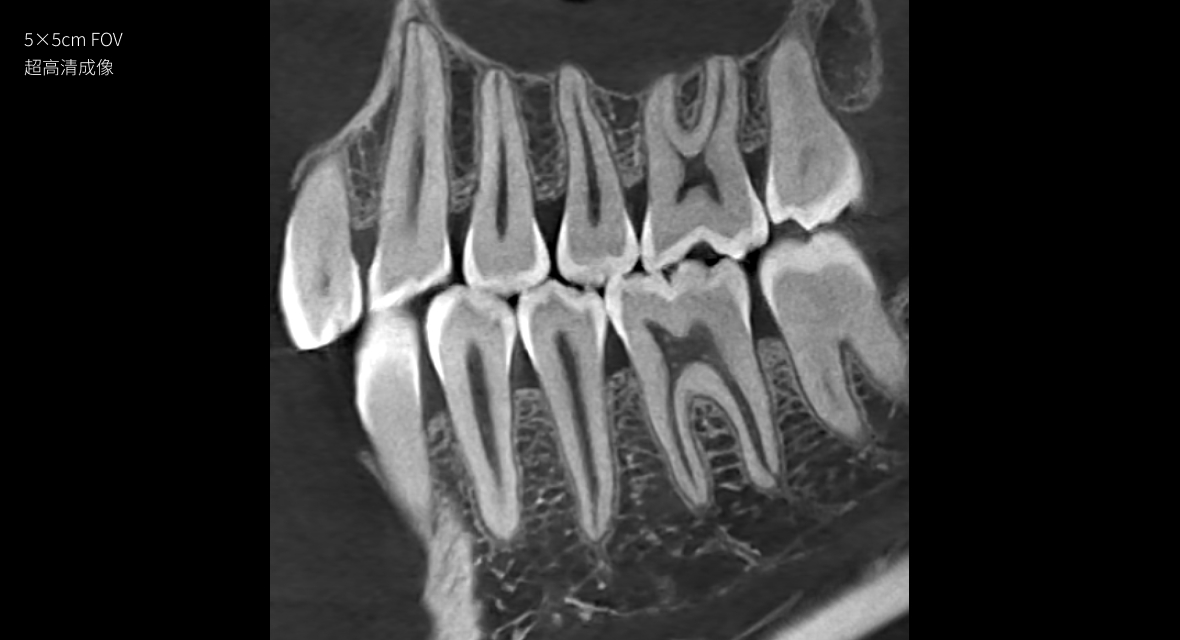

• 旋转阳极射源——超高清成像

图像空间分辨率高达40lp/cm,“遥遥领先”

40lp/cm

超高清空间分辨率